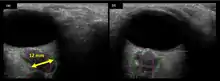

The astronauts affected by long term visual changes and prolonged intracranial hypertension have all been male, and SOS may explain this because in men, the sternocleidomastoid muscle is typically thicker than in women and may contribute to more compression. The reason that SOS does not occur in all individuals may be related to anatomic variations in the internal jugular vein. Ultrasound study has shown that in some individuals, the internal jugular vein is located in a more lateral position to Zone I compression, and therefore not as much compression will occur, allowing continued blood flow.

The first U.S. case of visual changes observed on orbit was reported by a long-duration astronaut that noticed a marked decrease in near-visual acuity throughout his mission on board the ISS, but at no time reported headaches, transient visual obscurations, pulsatile tinnitus or diplopia (double vision). His postflight fundus examination (Figure 1) revealed choroidal folds below the optic disc and a single cotton-wool spot in the inferior arcade of the right eye. The acquired choroidal folds gradually improved, but were still present 3 year postflight. The left eye examination was normal. There was no documented evidence of optic-disc edema in either eye. Brain MRI, lumbar puncture, and OCT were not performed preflight or postflight on this astronaut.[5]